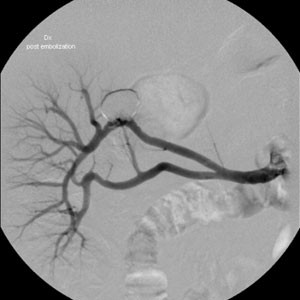

Fig. 4.